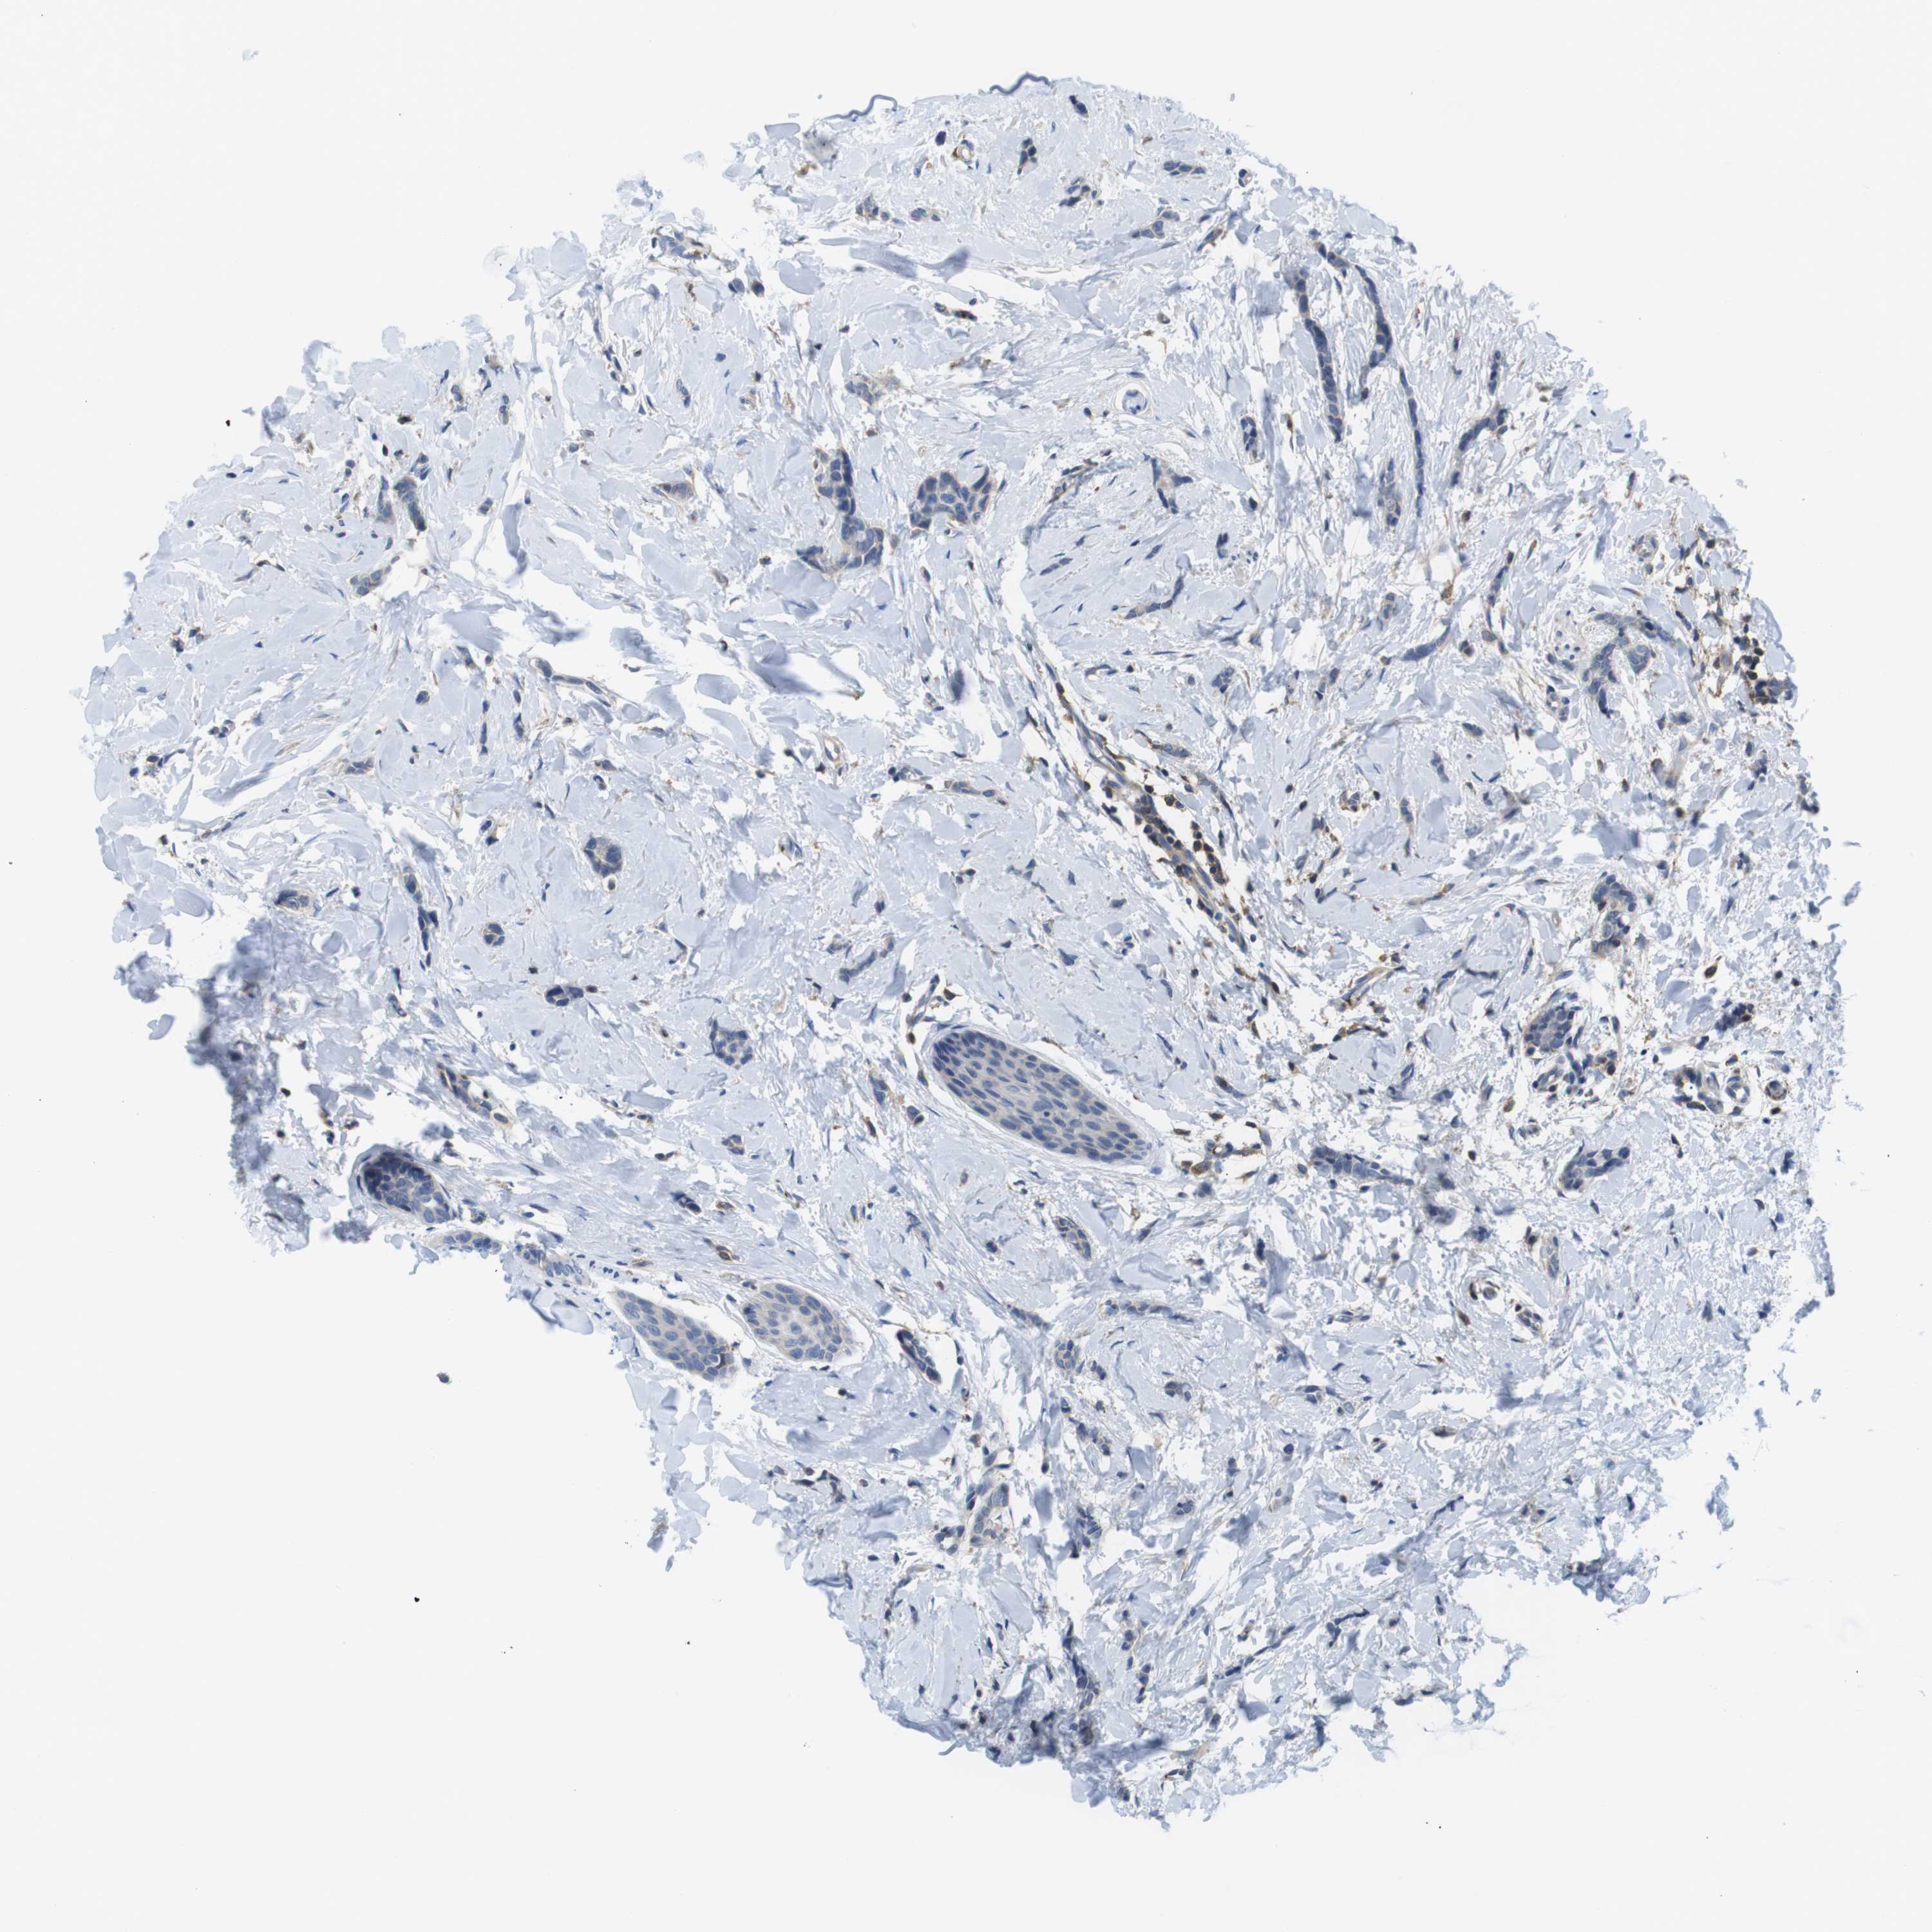

CANCER BREAST CANCER Show tissue menu

BRCA TCGA BRCA VALIDATION PROTEIN EXPRESSION